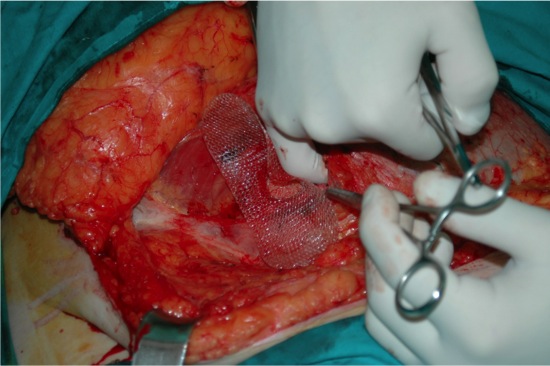

Imagen núm. 8: Expansión de la hoja inferior de la malla en el espacio preperitoneal.

Imagen núm. 9: Obturación del defecto herniario y expansión de la malla superficial PHS.